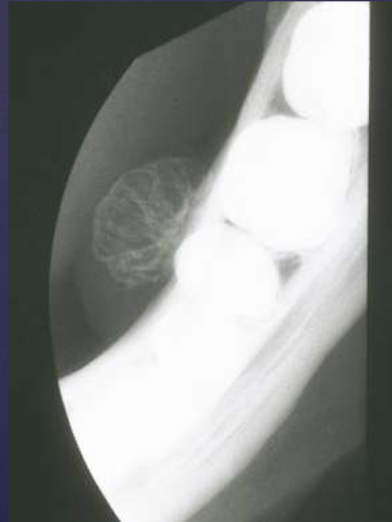

radiographic features of cementoblastomas

multiple punctate radiopacities within a well-defined radiolucency

homogeneous radiopaque mass

mass attached to 1st mandibular molar roots

obscured root outline, external resorption

radiolucent halo - continuity w/ PDL

sclerotic border